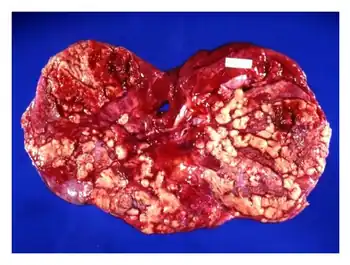

- Tubercular lymphadenopathy: Abdominal lymphadenopathy is the most common manifestation of abdominal tuberculosis. The commonly involved lymph nodes are mesenteric nodes and omental nodes. They usually have central areas of caseous necrosis.[4][3]

- Visceral tuberculosis: This type involves the solid organs in the abdomen, either in isolation or as part of a more widespread infection. Common organs affected include the liver, spleen, and pancreas, as well as the genitourinary system (kidneys, bladder)[3][9][4]